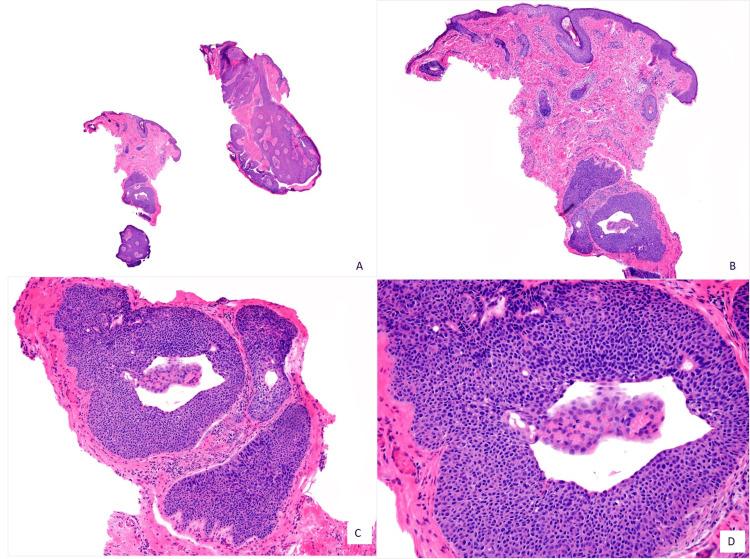

Eccrine poroma is a rare benign adnexal tumor arising from intradermal cells of eccrine sweat ducts. At least two-thirds of eccrine poromas present on the extremities, most commonly on the palms and soles. They are scarcely found on the face; to date, only 11 cases of eyelid poromas have been reported in PubMed. Biopsy excision with a free margin is necessary to distinguish it from malignant lesions and avoid recurrence with possible transformation to porocarcinoma. We present the case of a 23-year-old male with a histopathological confirmation of poroma using staining with hematoxylin-eosin on the eyelid, previously clinically diagnosed with molluscum contagiosum. After four years, he has not experienced a recurrence.

小汗腺汗孔瘤是一种罕见的良性附属器肿瘤,起源于小汗腺导管的真皮内细胞。至少三分之二的小汗腺汗孔瘤出现在四肢,最常见于手掌和足底。面部很少见;迄今为止,PubMed上仅报道了11例眼睑汗孔瘤。为了将其与恶性病变区分开来并避免可能转化为汗孔癌的复发,需要进行切缘阴性的活检切除。我们报告了一例23岁男性病例,其眼睑经苏木精-伊红染色组织病理学确诊为汗孔瘤,此前临床诊断为传染性软疣。四年后,他未出现复发。